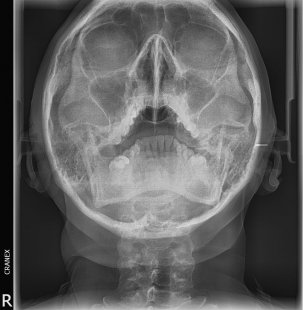

- RX. Frontal (Postero-anterior)